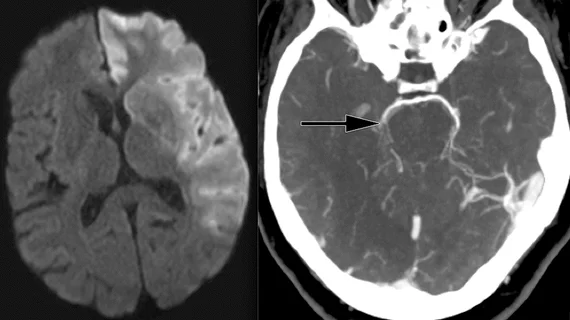

Neuroradiology is a branch of medical imaging focused on spotting abnormalities of the central and peripheral nervous system, spine, head and neck. These highly trained doctors use CT, MRI, X-ray and other techniques to diagnose strokes, tumors, aneurysms and other neurological conditions.